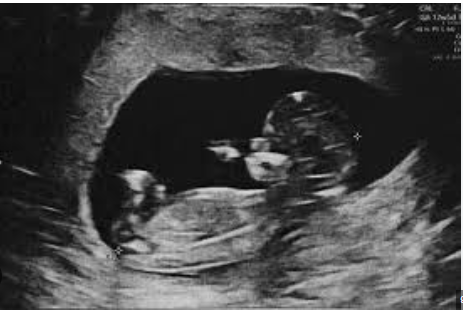

„Na monitoru jasno vidim tri fetusa. Čestitam – nosite trojke!“

U trenutku, soba se zavrtjela. Marina je gledala ekran, pokušavajući razaznati oblike koji su se kretali u crno-bijelim sjenama. Trojke. Tri srca. Tri života. Tihi šok ispunio je prostor, a onda su krenule suze – suze nevjerice, straha, ali i neobjašnjive radosti.